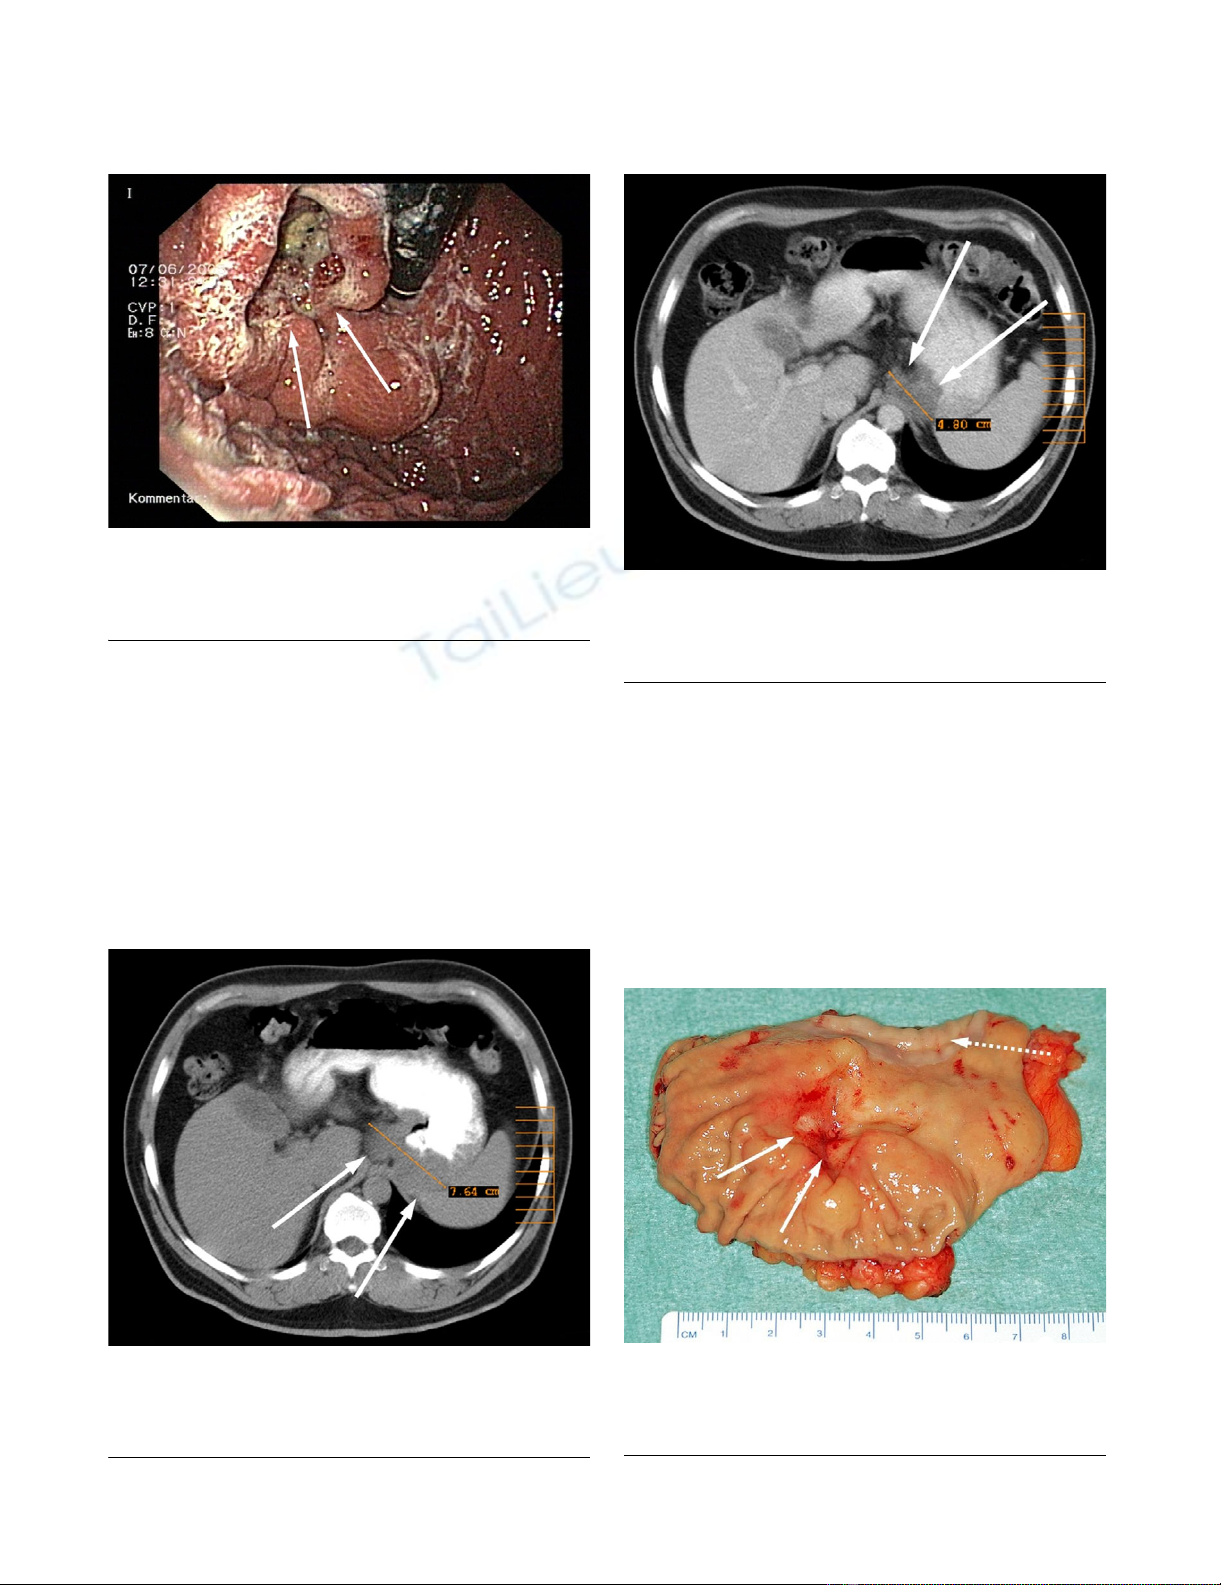

Initial CT-ScanFigure 2

Initial CT-Scan. Initial CT scan showing the advanced

tumor of the esophagogastric junction before starting neoad-

juvant therapy.

multislice computerized tomography (CT) showed a solid

tumor measuring 7.6 cm extending from the distal

esophagus to the gastric cardia and fundus with extension

into of the left diaphragmatic muscular column and the

splenic hilus (figure 2). Surgery with curative intent at this

Postoperative specimenFigure 4

Postoperative specimen. Postoperative specimen show-

ing the residual ulcerous lesion and esophageal mucosa in the

upper part (interrupted arrow).